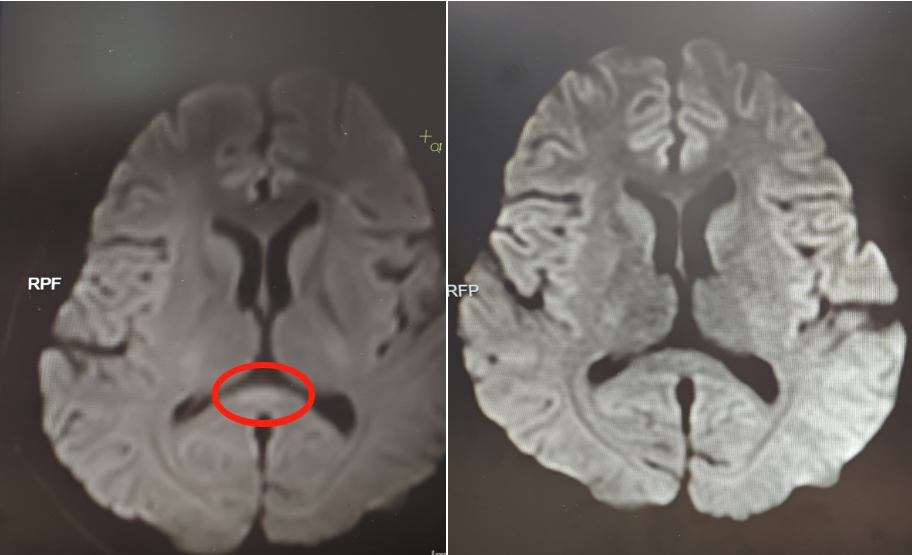

▲治疗前(左)核磁共振提示胼胝体压部病变

该院神经内六科医生接诊后,初步判断为脑炎。完善血清、脑脊液检测等,结果不支持颅内感染及自身免疫性脑炎,进一步完善细胞因子等炎症指标,结合核磁共振等,最终诊断阿婷为副感染性脑病。

好在接受相应治疗后,阿婷的意识逐渐恢复,情绪日趋稳定,已于近日康复出院。